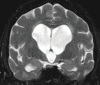

Neurodegenerative diseases are a devastating group of disorders that can be difficult to accurately diagnose. Although these disorders are difficult to manage owing to relatively limited treatment options, an early and correct diagnosis can help with managing symptoms and coping with the later stages of these disease processes. Both anatomic structural imaging and physiologic molecular imaging have evolved to a state in which these neurodegenerative processes can be identified relatively early with high accuracy. To determine the underlying disease, the radiologist should understand the different distributions and pathophysiologic processes involved. High-spatial-resolution MRI allows detection of subtle morphologic changes, as well as potential complications and alternate diagnoses, while molecular imaging allows visualization of altered function or abnormal increased or decreased concentration of disease-specific markers. These methodologies are complementary. Appropriate workup and interpretation of diagnostic studies require an integrated, multimodality, multidisciplinary approach. This article reviews the protocols and findings at MRI and nuclear medicine imaging, including with the use of flurodeoxyglucose, amyloid tracers, and dopaminergic transporter imaging (ioflupane). The pathophysiology of some of the major neurodegenerative processes and their clinical presentations are also reviewed; this information is critical to understand how these imaging modalities work, and it aids in the integration of clinical data to help synthesize a final diagnosis. Radiologists and nuclear medicine physicians aiming to include the evaluation of neurodegenerative diseases in their practice should be aware of and familiar with the multiple imaging modalities available and how using these modalities is essential in the multidisciplinary management of patients with neurodegenerative diseases.©RSNA, 2020.